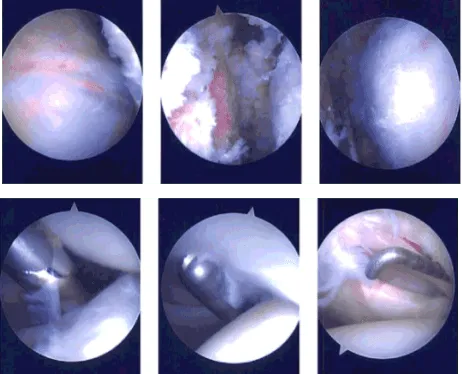

Se realizó una incisión posterior a través del punto para la puerta de entrada del endoscopio. El endoscopio se introdujo en la articulación glenohumeral y se examinó la articulación glenohumeral. Hubo desgarros del labrum así como desgarros del manguito rotador en el sitio articular. El desbridamiento se realizó usando una afeitadora. Los bíceps estaban intactos.

El tendón subescapular, así como el ligamento glenohuméral inferior y el ligamento glenohuméral superior, permanecieron intactos. Hubo cambios condrales degenerativos de grado 1 a grado 2 usando una afeitadora. Ahora, el endoscopio se introdujo en la zona subacromial donde estaba presente la bursitis subacromial.

Se utilizó afeitador para descomprimir la región subacromial y se realizó una bursectomía. Se encontraron espolóns acromiales y acromión tipo 2. Se utilizó una muela para realizar la acromioplastia. Se encontró que la articulación AC estaba intacta y no se detectó inflamación. Se tomaron las fotos finales.

Imágenes de artroscopia intraoperatoria